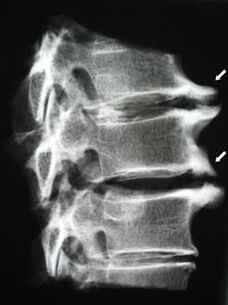

Nelle fasi iniziali, l'osteocondrosi viene rilevata mediante risonanza magnetica. Successivamente, la patologia può essere diagnosticata mediante radiografia. Nelle radiografie della colonna cervicale si notano una riduzione della distanza tra le vertebre, cambiamenti patologici nelle articolazioni delle faccette e osteofitosi.

Molte persone si lamentano di non riuscire a girare il collo a causa del forte dolore quando improvvisamente sollevano qualcosa di pesante. Questo fenomeno indica lo sviluppo di un'ernia del disco. La causa del dolore alla schiena, al collo e agli arti superiori è il pizzicamento di una delle radici nervose che escono dal midollo spinale.